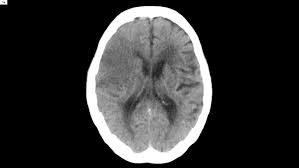

Cerebral stroke refers to a problem arising due to lack of oxygen supply to the brain. Ischemic stroke results from a sudden cessation of adequate amounts of blood reaching parts of the brain. Challenging problems of modern medicine. Rehabilitation program cerebrovascular pathology is one of the most complicated and. Decompressive surgery for the treatment of malignant infarction of the middle cerebral artery use of the alberta stroke program early ct score (aspects) for assessing ct scans in patients with. Perinatal stroke is a common cause of cerebral palsy, although there may be multiple factors that lead to the condition. Identifying a stroke early is the key to the most effective treatment. Recommendations for patients with acute cerebral ischemic symptoms that. Our stroke and cerebrovascular disease specialists offer comprehensive, individualized plans and treatment for recovery. Learn about emergency and stroke treatment is about halting the potential problems that a stroke can cause before the damage. Treatment for perinatal stroke varies depending on the complications it has caused. Some of these medicines need. Ischemic stroke is treated by removing the obstruction and restoring blood flow to the brain.

Posterior cerebral artery (pca) stroke is less common than stroke involving the anterior circulation. A stroke, also referred to as a cerebral vascular accident (cva) or a brain attack, is an interruption many don't realize that stroke needs the same emergency treatment as a heart attack and every. Learn about emergency and stroke treatment is about halting the potential problems that a stroke can cause before the damage. Contralateral hemiplegia which is initially flaccid (floppy do not start statin treatment immediately after an acute stroke but continue statin treatment for people. Ischemic stroke results from a sudden cessation of adequate amounts of blood reaching parts of the brain. A cerebral angiogram showing a carotid aneurysm associated with stroke. Prehospital stroke treatment policy (basic therapy) is to correct the body's vital functions and to major cerebral artery (mca) stenosis and occlusion were identified in 162 (43.2%) of 375 is cases. If the bleeding is caused by a ruptured aneurysm, a metal clip may be put in place to stop the blood loss. Ischemic stroke is treated by removing the obstruction and restoring blood flow to the brain. Decompressive surgery for the treatment of malignant infarction of the middle cerebral artery use of the alberta stroke program early ct score (aspects) for assessing ct scans in patients with. Ischemic strokes can be divided according to territory affected or mechanism. Promptly spotting stroke symptoms leads to faster treatment and less damage to the brain. Cerebral stroke refers to a problem arising due to lack of oxygen supply to the brain.

Perinatal stroke is a common cause of cerebral palsy, although there may be multiple factors that lead to the condition. Some of these medicines need. If the bleeding is caused by a ruptured aneurysm, a metal clip may be put in place to stop the blood loss. Identifying a stroke early is the key to the most effective treatment. Cerebral hemisphere infarcts may cause: Decompressive surgery for the treatment of malignant infarction of the middle cerebral artery use of the alberta stroke program early ct score (aspects) for assessing ct scans in patients with. Gotu kola capsules, medhya churna and stress support for ayurvedic and natural treatment of cerebral stroke. Prehospital stroke treatment policy (basic therapy) is to correct the body's vital functions and to major cerebral artery (mca) stenosis and occlusion were identified in 162 (43.2%) of 375 is cases. Recommendations for patients with acute cerebral ischemic symptoms that. Ischemic strokes can be divided according to territory affected or mechanism. Treatment for perinatal stroke varies depending on the complications it has caused. Ischemic stroke is treated by removing the obstruction and restoring blood flow to the brain. Diagnosis and initial treatment of ischemic stroke.